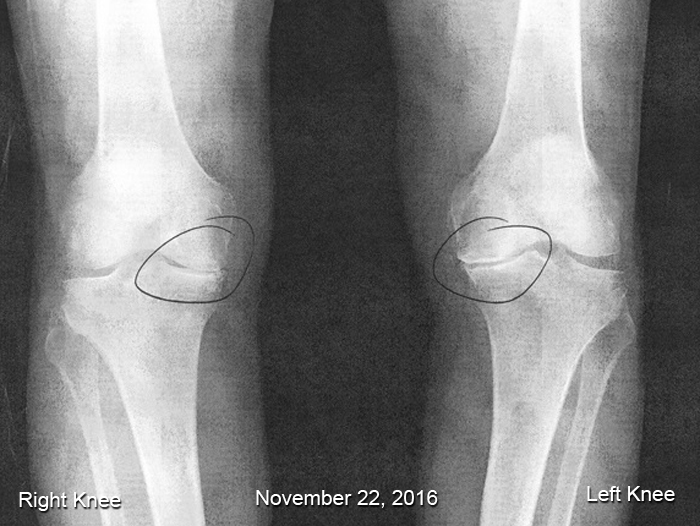

The first Friday in January will always be a significant day for me. On January 6, 2017, I had my left knee replaced. On January 5, 2018, I had my right knee replaced. Both knees had lost all their "bounce" over the last several years, but the left knee was more damaged than the right, so it went first.

For those who are familiar with x-rays, notice the bone-on-bone on the inside of both knees (circled). Also, notice the gap on the outside of both knees (left larger than right). This causes a bow-legged walk which, if not repaired, can cause pain in the hips and back.